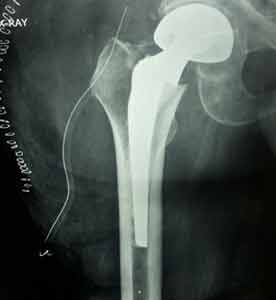

Case:10 Pathological Fracture

Seconderies from CA Prostate in 65 years old male patient treated with cemented bipolar prosthesis.

Pre-op

Post-op X-ray